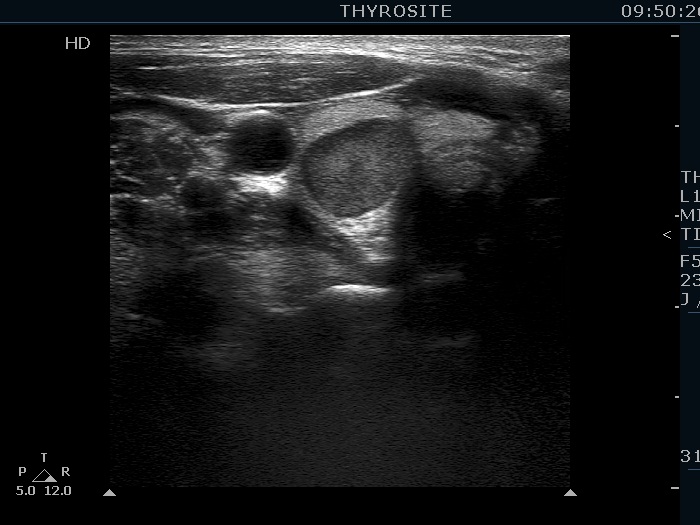

Ultrasonography. The thyroid was echonormal. There was a hypoechoic mass within the lower pole of the right lobe. The lesion was surrounded by thyroid tissue throughout.